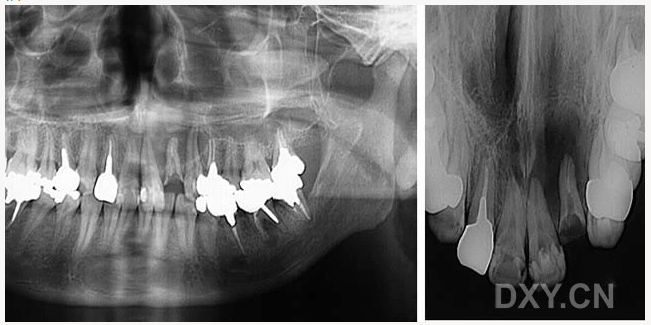

頜骨骨折